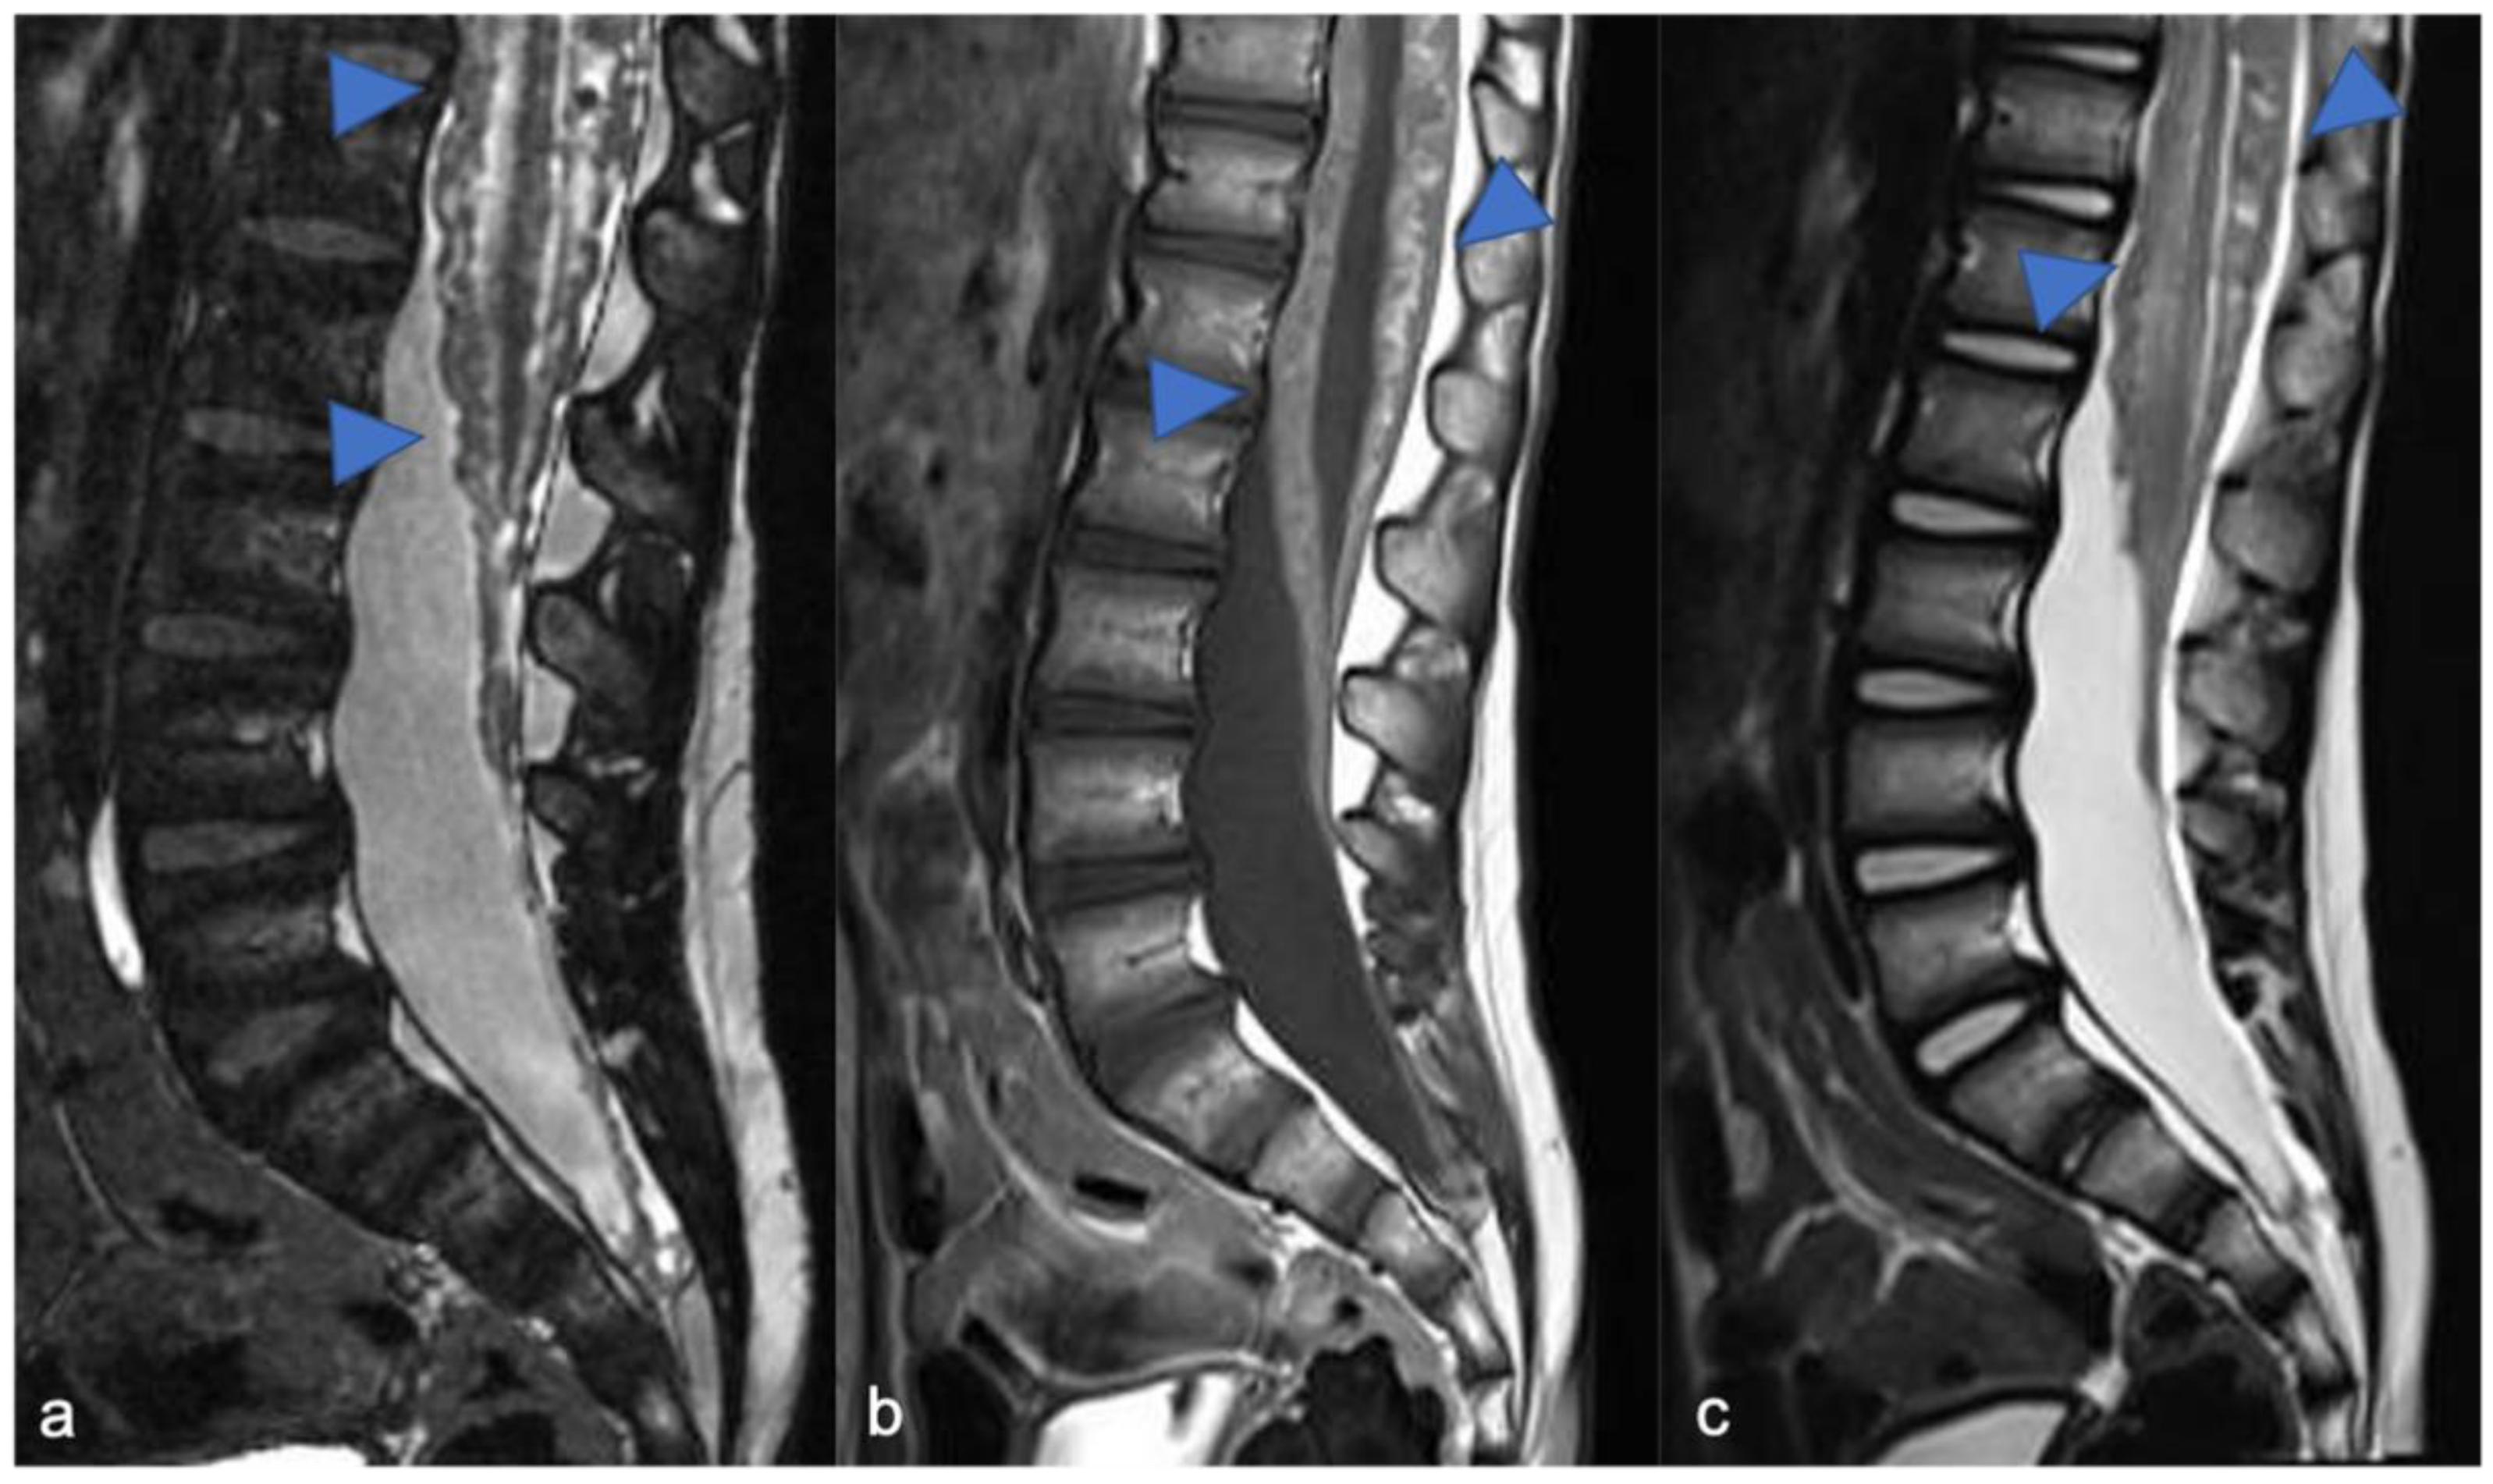

Astrocytomas are the most common pediatric intramedullary spinal tumors (approximately 60%) [1,2,7] and are frequently found in the first decade of life [3]. Among pediatric low-grade gliomas (pLGGs), defined as World Health Organization (WHO) grade I or II malignancies encompassing a wide array of histologies, the pilocytic histological subtype is commonly diagnosed in the first five years of life, while the fibrillary subtype is found at age of 10, accounting for 75% and 7% of all intrinsic pediatric spinal cancer, respectively [3,8]. High-grade gliomas (HGGs), defined from the WHO as grade III and IV, are very uncommon. Pilocytic astrocytoma is usually located at the cervicomedullary or cervicothoracic junction, and shows (i) “expansive” rather than “infiltrative” features (Figure 1), with (ii) spinal cord parenchymal “epicenter”, (iii) eccentric growth, and (iv) well-demarcated margins [3,7]. The swelling spine appearance could extend through several vertebral segments (usually < 4) [7], up to being holocordal—in this case it is important (but often complicated and not feasible) to distinguish between tumor and neoplastic edema [3]. The neoplasm could be predominantly (i) solid (40% of cases), (ii) necrotic cystic (60% of cases), or (iii) nodular cystic (Figure 2). Therefore, it could appear (i) iso/hypointense in T1 and hyperintense in T2 or (ii) hyperintense in T1 and T2, respectively [3]. The contrast enhancement is absent in 30% of cases [9] and, when present, is variable and depends on the different components. However, it is less evident than that of ependymomas [7]. Outcome of pLGGs depends on the extention of surgical resection and the success of the therapies—sometimes it is difficult to have a complete total resection. Near total resection is correlated with a 5-year progression free survival of up to 80% and overall survival of up to 95% [7].

Figure 1.

Pilocytic astrocytoma in a two-year-old child. Sagittal T2-weighted (a) and post-contrast T1-weighted (b) images show intramedullary hyperintense mass with inhomogeneous contrast enhancement, respectively (arrowheads). There is perilesional spinal cord edema (arrow).

Figure 2.

Pilocytic astrocytoma in an eight-year-old child, including expansive mass and distinct solid cystic components at level D11-12. Sagittal T1-weighted (a), T2-weighted (b), and post-contrast T1-weighted (c) images demonstrate a cystic-like cranial component with evident and homogeneous enhancement (arrowheads) and a caudal solid component without enhancement (arrows).